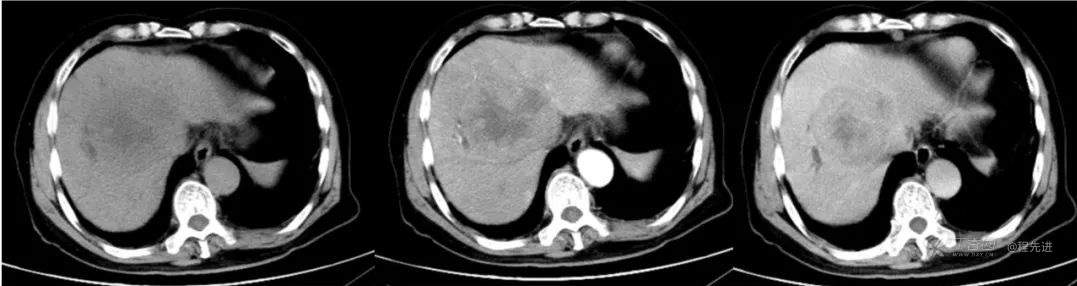

红五月特别精彩病例|胸部不适CT检查发现肝门区占位【病理已公布】

简要病史:因胸部不适入院,胸部CT示:肺部感染性病变;腹部CT示:肝门区占位性病变

既往史:有乙型肝炎病毒感染病史,未接受系统治疗

辅助检查:白细胞12.33×10^9/L 谷丙转氨酶 70u/L 谷草转氨酶90u/L